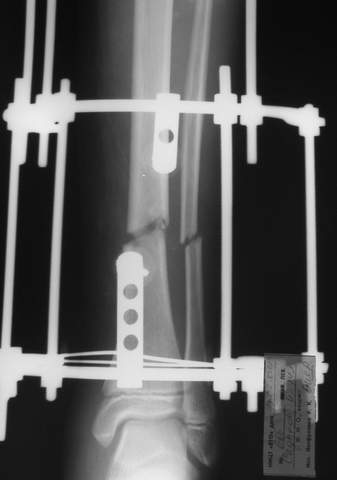

Уважаемый Виталий Евгеньевич,

Помятуя наш недавний разговор о фиксации м.б. кост, высылаю послеоперационные картинки..

Напомню- разбирали случай 17 летнего молодого человека перелом дист тиб.фиб. хирургия после 3 недель с момента травмы( безуспешные попытки закрытой репозиции) Раны заживают первичным натяжением, занимается физиотерапией, пока никаких проблем не наблюдается

Как ты тут оцениваешь восстановление оси большеберцовой кости?

Является ли рутинной практикой у вас использовать снимок противоположной конечности как шаблон для измерения осевых отклонений?

Отправитель: Evgueny Tchekashkine 01 Апрель 2005, 22:45

Согласный я с тобой:-)) есть остаточная вальгусная деформация (по снимку видно перекрывание дист. фрагментом б.б по латеральной поверхности проксимальноо фагмента на 2-3 мм и наружная лодыжка репонирована с укорочением, судя по прямой проекции. Необходимость использования интраоперационно дистрактора была бы оправдана (вручную было непросто *вытянуть* дистальный отломок.)

> Является ли рутинной практикой у вас использовать снимок

> противоположной конечности как шаблон для измерения осевых

> отклонений?

Нет, рутинным не назовешь, в данном случае отклонение оси видно и невооруженным взглядом без сравнения со здоровой стороной. Сравнительную осевую оценку со здоровой стороной использую только при планировании коррегирующих остеотомий.